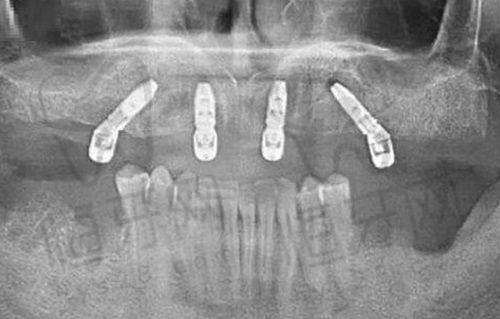

在太原市口腔医院排名中,山西医 科 大学第一医院口腔科可是当之无愧的老大!它是山西省口腔医学重点学科,医疗质量和规模在全省那都是领跑水平。这里亚专科设置齐全,涵盖了10个二级学科和2个病区,就像一个口腔领域的“超级航母”,能全方面满足咱各种口腔需求。

特色亮点:一是技术领跑,先开展了即刻种植即刻负重、前牙美学种植、复杂植骨术等一系列高难度技术。想象一下,种牙不用等那么久就能修复正常使用,前牙修复后还能美美哒,这技术多牛!二是科研实力突出,近五年在省内同级医院中科研产出排名前位,这说明人家不仅会看病,还在不断探索口腔医学的新领域。

山西大医院口腔科在口腔种植和口腔颌面肿 瘤治疗方面有一定的优势。口腔种植能让缺失牙齿的患者重新拥有健康的牙齿,而口腔颌面肿 瘤治疗则关系到患者的生命健康。

特色亮点:一是口腔种植技术成熟,种植成功几率高。二是在口腔颌面肿 瘤的诊断和治疗上有专精的团队,能为患者提供综合的治疗方案。